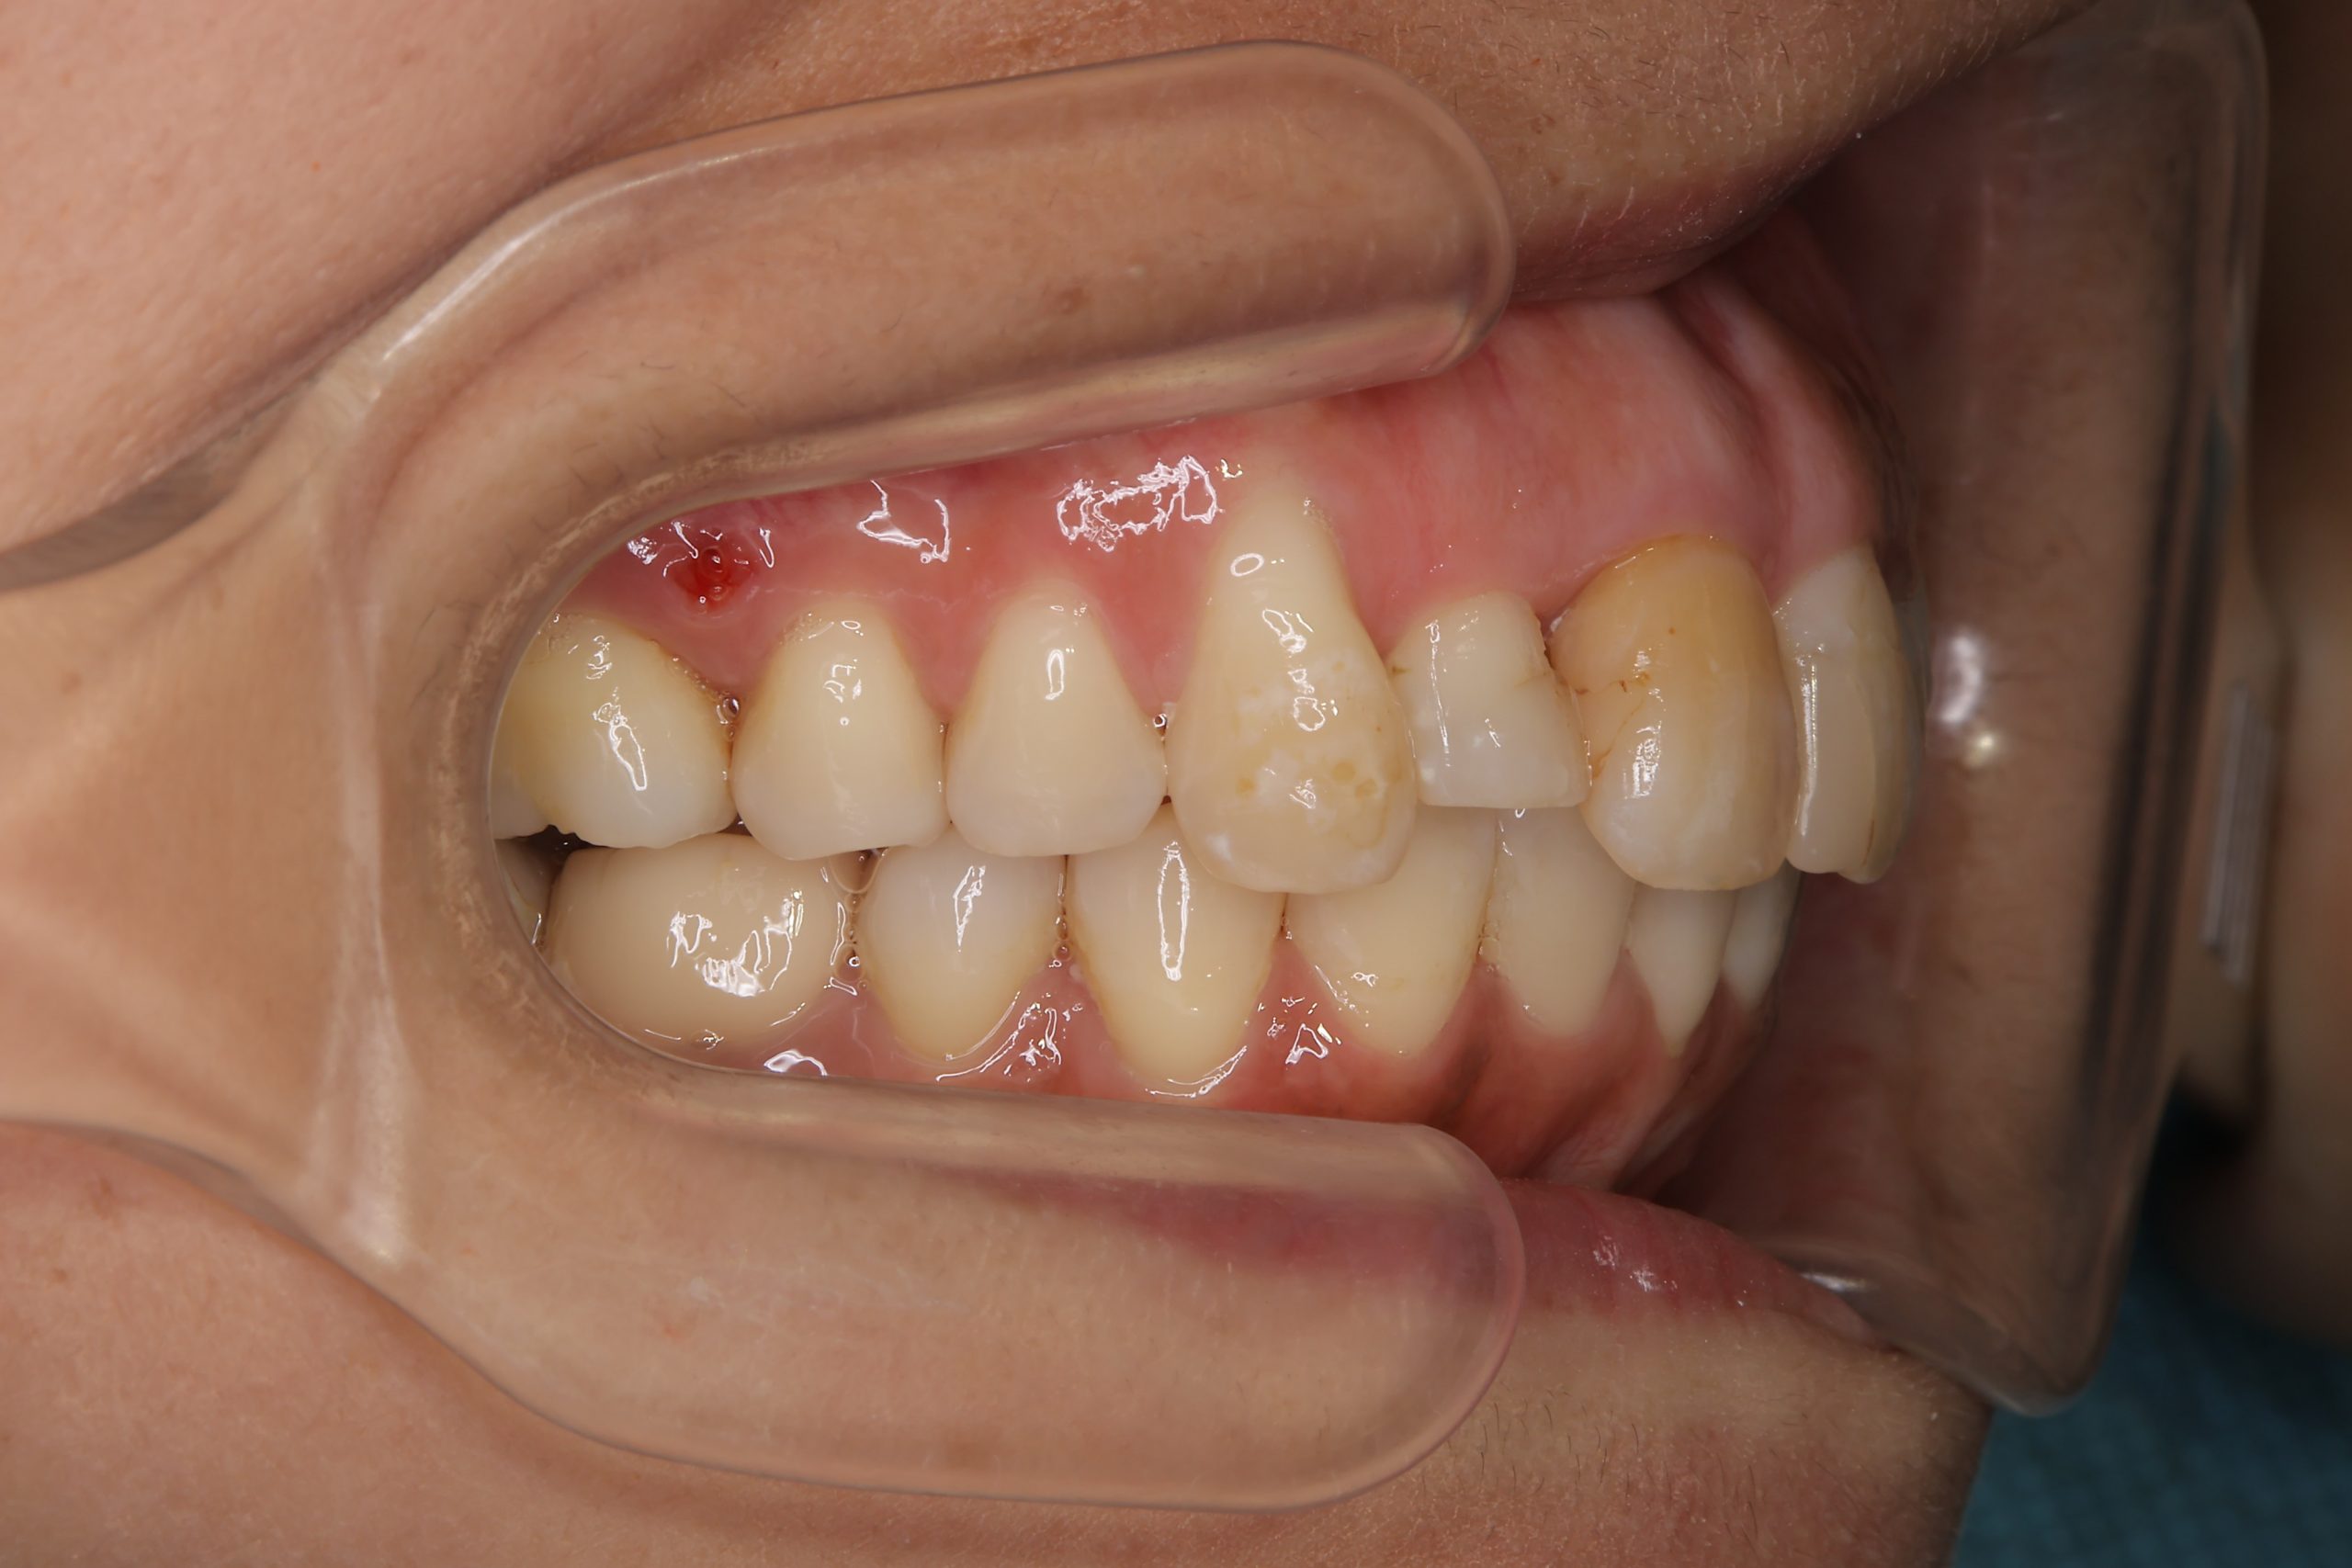

ビフォー

インビザライン矯正治療|症例_649